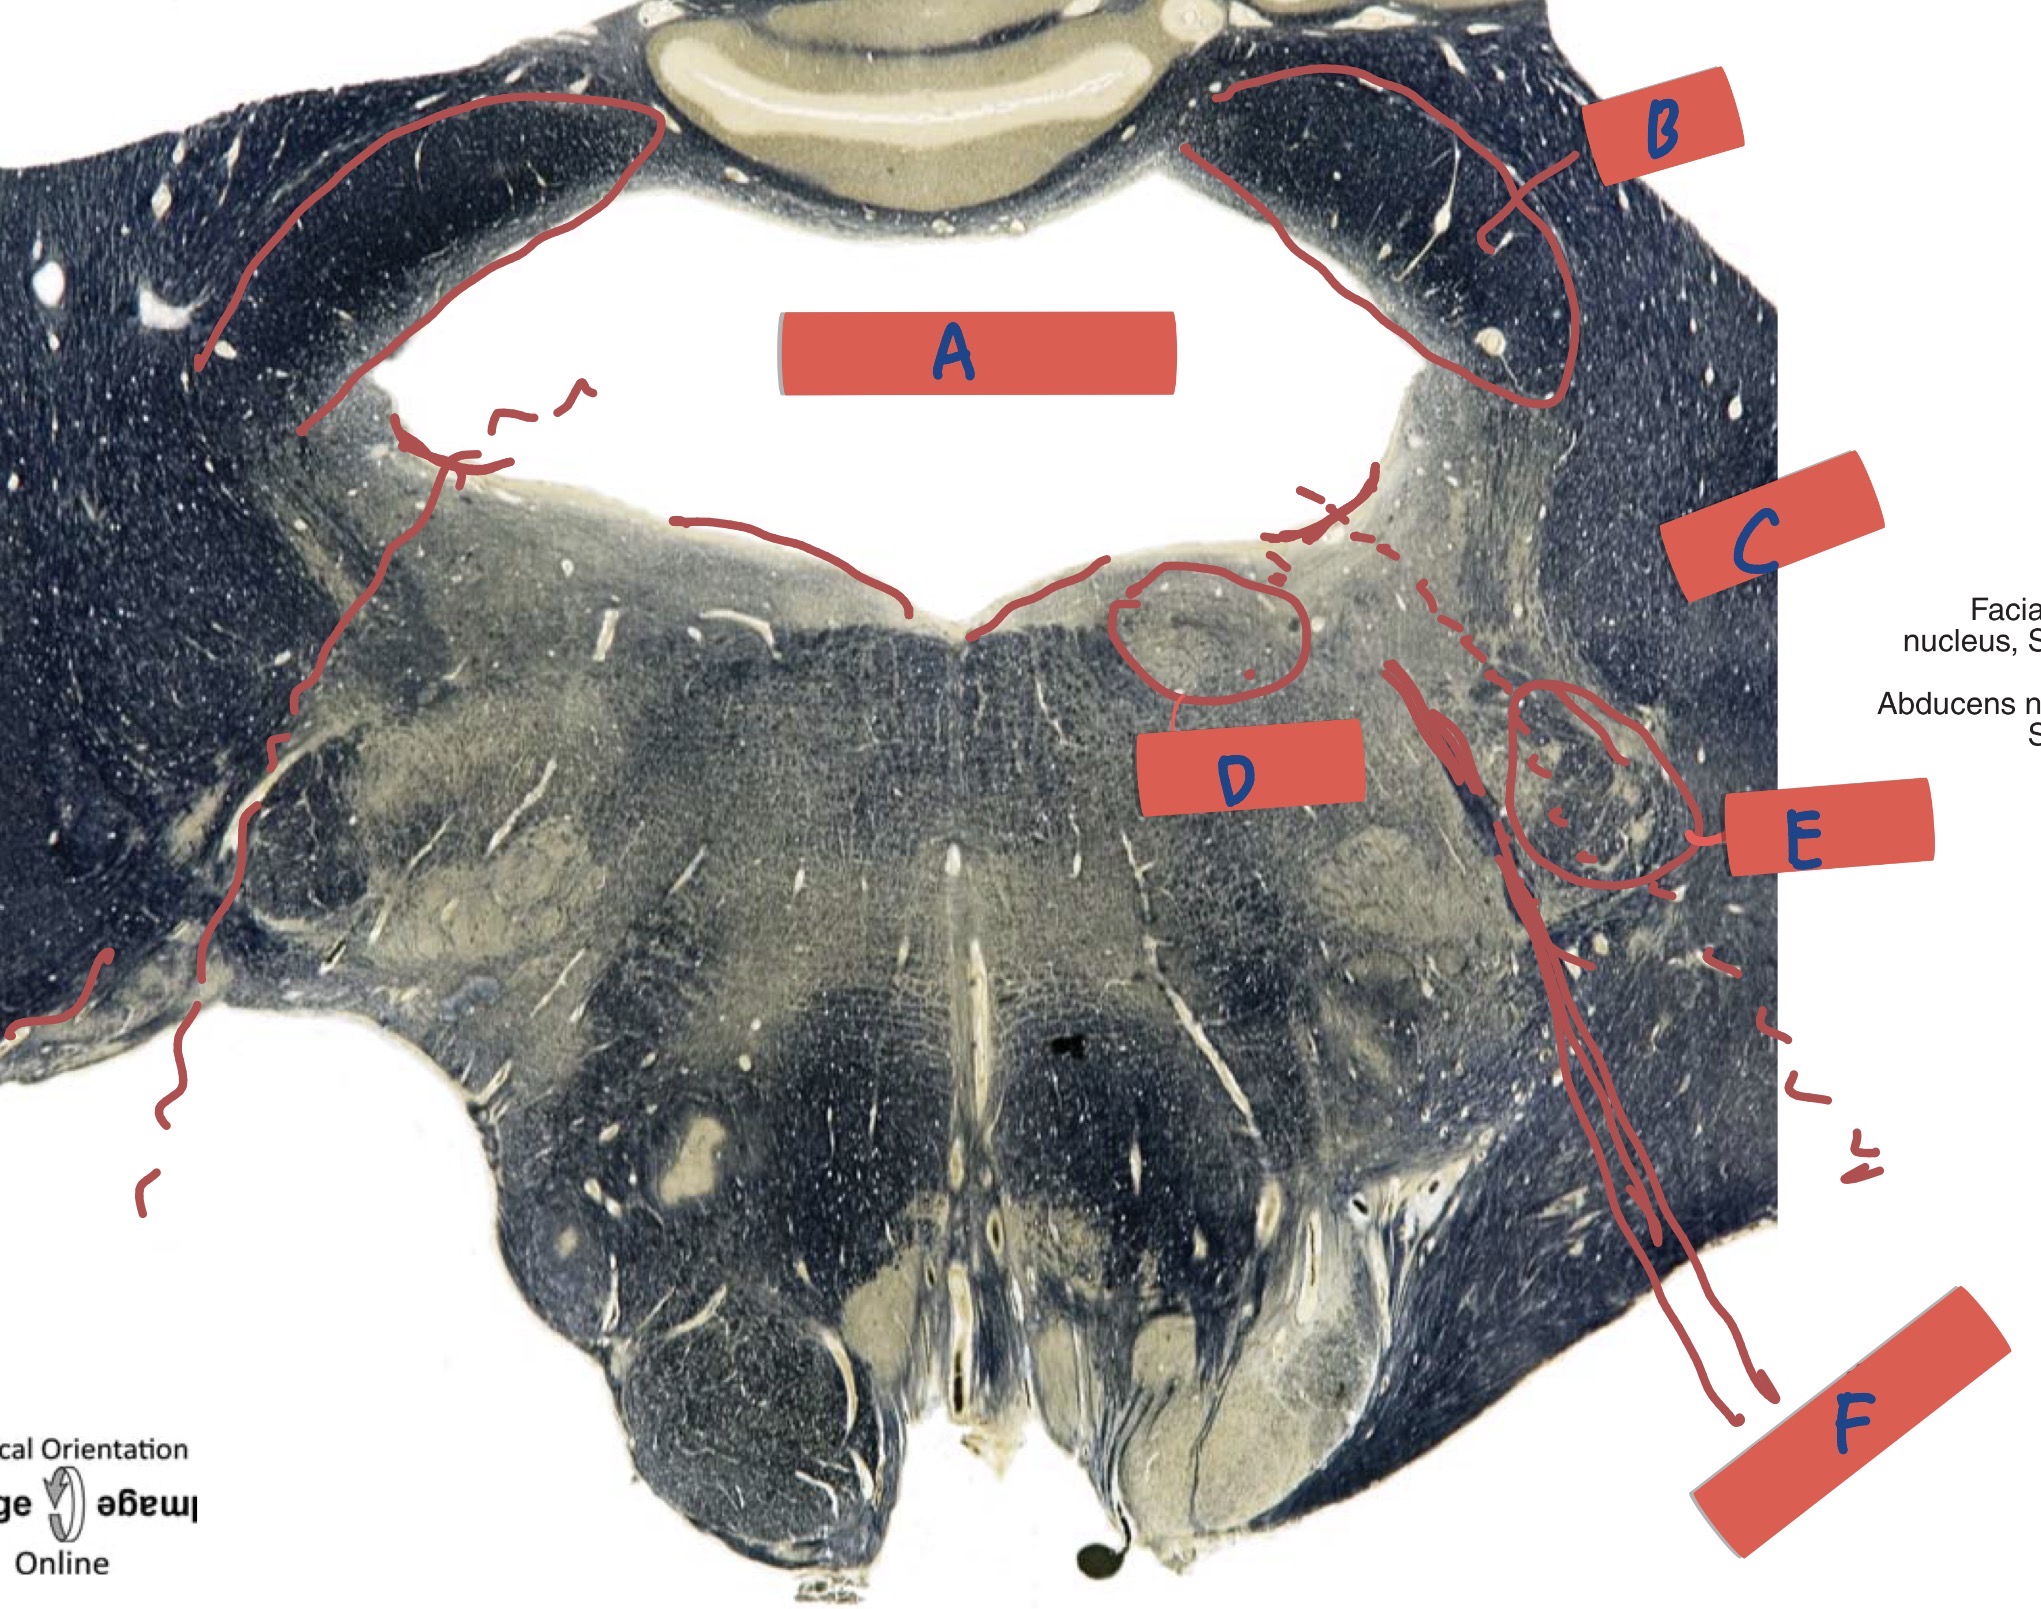

What is A?

Forth Ventricle

What is B?

Superior cerebellar peduncle

What is C?

Inferior cerebellar peduncle

What is D?

Abducen nucleus

What is E?

Facial nucleus

What is F?

Facial nerve fibre

What level is this?

Rostal pons